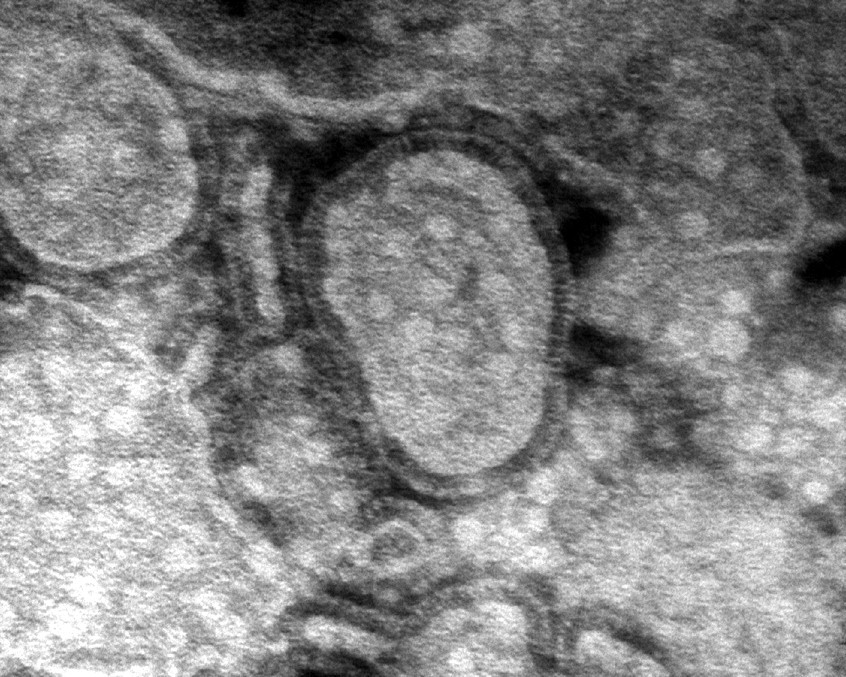

Угрожает ли миру новая пандемия из-за вируса hMPV 03 июня 2023, 02:00 0 03 июня 2023, 02:00 Новости hi tech и софта Jony 412 0 Фитнес здоровье Угрожает миру новая hMPV Новости 03/12/2025 Микроразметка Schema.org: почему без нее сайты теряют трафик и как внедрить ее без головной боли 03/12/2025 ИИ-фотосессия в деловом стиле: гайд, готовые промпты, боты с бесплатными генерациями в Telegram 01/12/2025 Школы программирования: как выбрать путь в будущее IT Комментарии Сергей Гусев: 02/10/2025 Очень полезная статья для разработчиков PHP. Константин Золотухин ясно объясняет основные угрозы — Макс: 01/09/2023 Якщо у вас є погана кредитна історія, ви можете спробувати покращити її перед подачею заявки на Гость Дмитрий: 06/07/2023 Сергей если не жалко скиньте плз его на почту) venis29 на яндексе ваши контакты к сожалению не Добавить комментарий Нам важно знать ваше мнение. Оставьте свой отзыв или ответ Отправить комментарий Комментариев 0 Для полноценной работы с PHP-ru.info войдите на сайт с помощью социальных сетей: